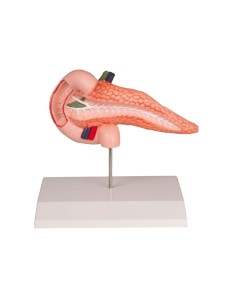

Dal cranio in 22 parti con incastri magnetici ai modelli di colonna vertebrale, da quelli di articolazioni a quelli di cuore, ogni pezzo della nostra collezione è progettato per un’immersione totale nello studio dell’anatomia umana. I nostri modelli, realizzati tramite scansioni di ossa vere, garantiscono un’esperienza tattile autentica e una fedeltà di peso quasi identica agli originali.

Essenziali per studenti e professionisti, i nostri modelli anatomici sono strumenti didattici che permettono di osservare le strutture anatomiche con precisione, eliminando la necessità di dissezioni o studi invasivi. Sono inoltre utili per spiegare ai pazienti le patologie, rendendo la comunicazione più efficace e risparmiando tempo prezioso.